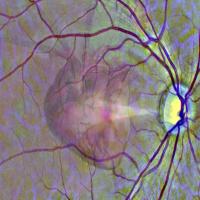

AI can identify heart disease from an eye scan

Scientists have developed an artificial intelligence system that can analyze eye scans taken during a routine visit to an optician or eye clinic and identify patients at a high risk of a heart attack.